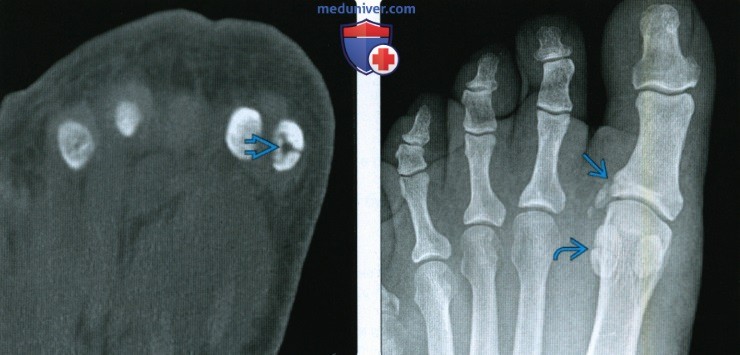

Перелом сесамовидной кости: Визуализация травмы и её лечение